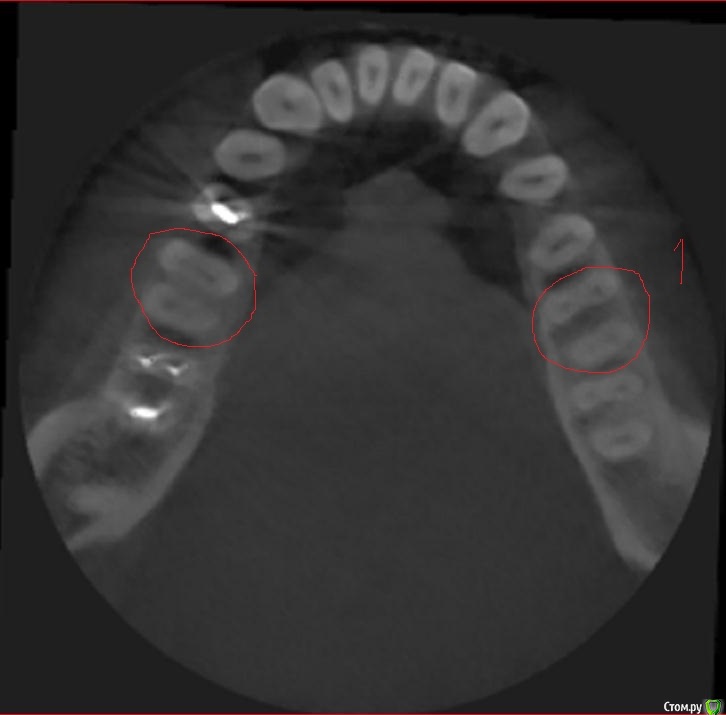

Svetic Опубликовано 16 августа, 2015 Поделиться Опубликовано 16 августа, 2015 (изменено) Здравствуйте, история такая. Отправилась лечить нижнюю шестерку. Выпала пломба, зуб реагировал на холодное и на накусываение. Врач поставила пломбу,депульпировать не стала. Зуб заболел через два дня. Четыре дня назад удалили нерв, реакция зуба на холодное осталась. Позвонила по телефону врачу, говорит что после мышьяка болеть зуб не может. Мог ли врач пропустить один канал? Нашла томограму которую делала 3 месяца назад. Скажите пожалуйста сколько в шестерках каналов? Врач пролечила 3 канала. Тот зуб под номером 1 еще до лечения. Изменено 16 августа, 2015 пользователем Svetic Ссылка на комментарий

St. Опубликовано 16 августа, 2015 Поделиться Опубликовано 16 августа, 2015 Каналов 4. КТ доктор во время лечения видел? Ссылка на комментарий